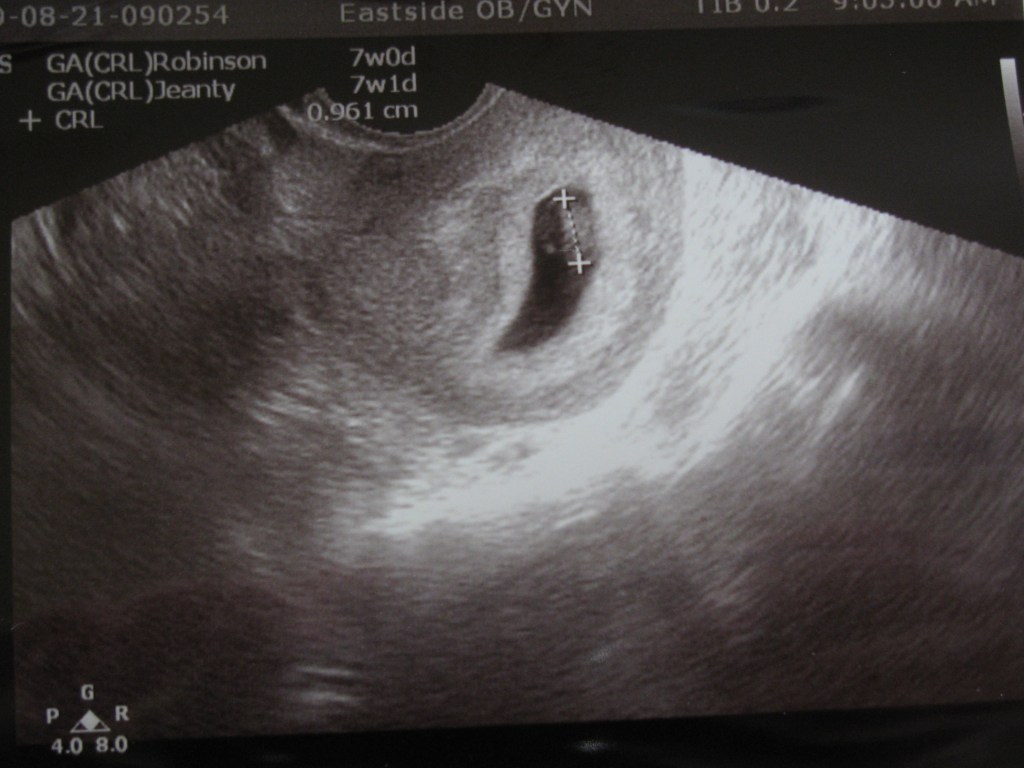

Pictures of the first glimpse of our second cute baby: